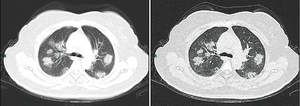

اقترحت الإرشادات التشخيصية الصادرة عن مستشفى تشونغنان بجامعة ووخان طرقًا للكشف عن العدوى بناءً على السمات السريرية والمخاطر الوبائية. تضمن هذا تحديد الأشخاص الذين لديهم على الأقل اثنين من الأعراض التالية بالإضافة إلى تاريخ من السفر إلى ووخان أو الاتصال بأشخاص آخرين مصابين: الحمى أوعلامات التصوير المقطعي للاتهاب الرئوي أو عدد خلايا الدم البيضاء الطبيعي أو المنخفض أو انخفاض عدد الخلايا الليمفاوية.[372] أظهرت دراسة نشرها فريق في مستشفى تونغجي في ووخان في 26 فبراير 2020 أن التصوير الطبقي المحوسب للصدر لـ COVID-19 لديه حساسية ونوعية أكثر (98٪) من تفاعل الپوليمريز المتسلسل (71٪).[373] قد تحدث نتائج سلبية كاذبة بسبب فشل مجموعة تفاعل الپوليمريز المتسلسل ، أو بسبب مشاكل في العينة أو مشاكل في إجراء الاختبار. من المرجح أن تكون النتائج الإيجابية الكاذبة نادرة..[374]

نتائج التصوير الطبقي المحوسب النموذجي

CT imaging of rapid progression stage